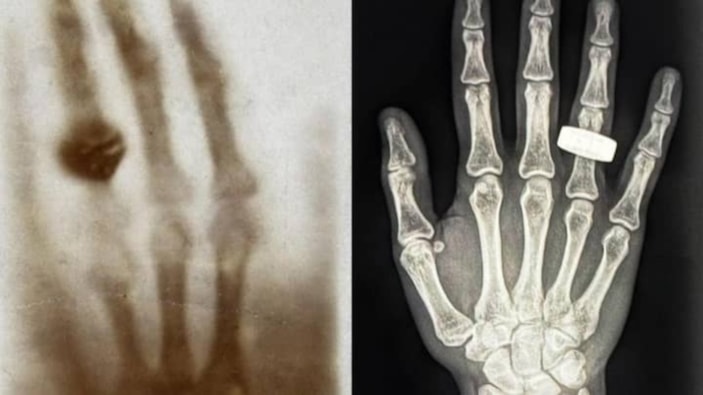

Uzayda çekilen ilk tıbbi röntgen, Fram2 görevinde gerçekleştirildi. Bu görüntü, yüzük takan bir elin gri tonlamalı taramasını içeriyor ve Wilhelm Roentgen'in 130 yıl önce çektiği orijinal röntgen filmini andırıyor.

Bu işlem, Dünya'nın yörüngesinde 28 bin km/saat hızla dönen dört kişilik bir kapsülün içinde, mikro yer çekiminde ve yüzeyden yaklaşık 320 km yükseklikte gerçekleştirildi.